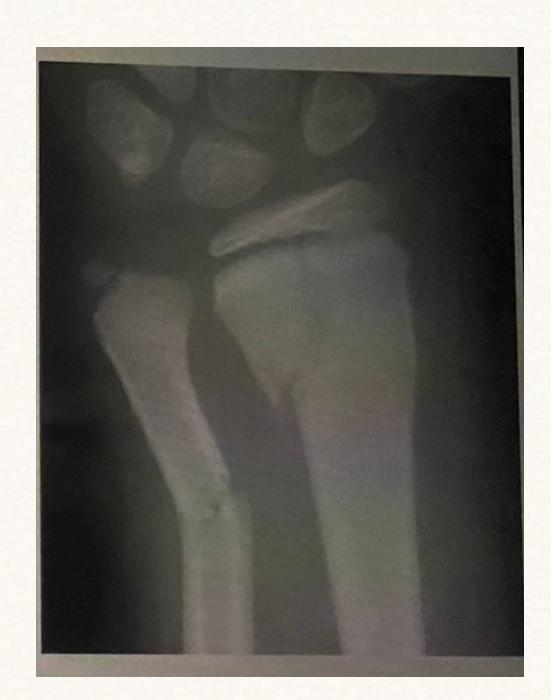

A 17-year-old male had a high ankle sprain followed by pain in his leg. X-ray films were obtained. According to the attached X-ray, which structure has been injured?

- B. Syndesmosis ligament

A 23-year-old male injured his ankle after a twisting ankle injury 2 days back. What is the most likely pathology based on shown x-ray?

Management Question: What is the management of the finding in the image?

- A. Screw fixation for syndesmosis injury